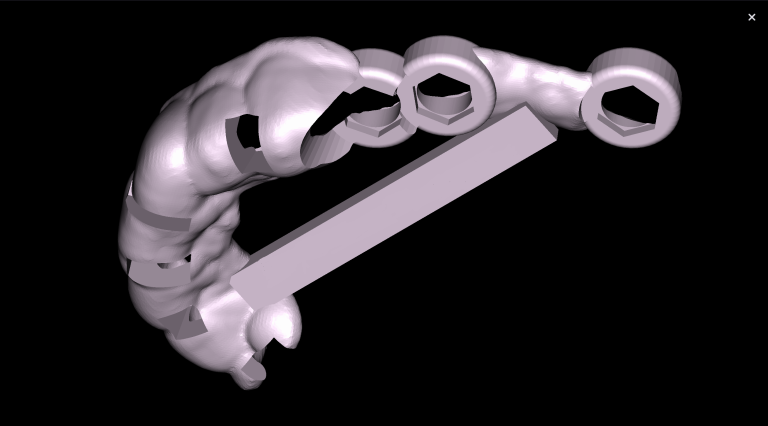

Virtual models of the template for guided implant surgery can be created using the “STL” module of Diagnocat. To do this, intraoral scan data is loaded into the module, and a suitable CBCT is selected for merging